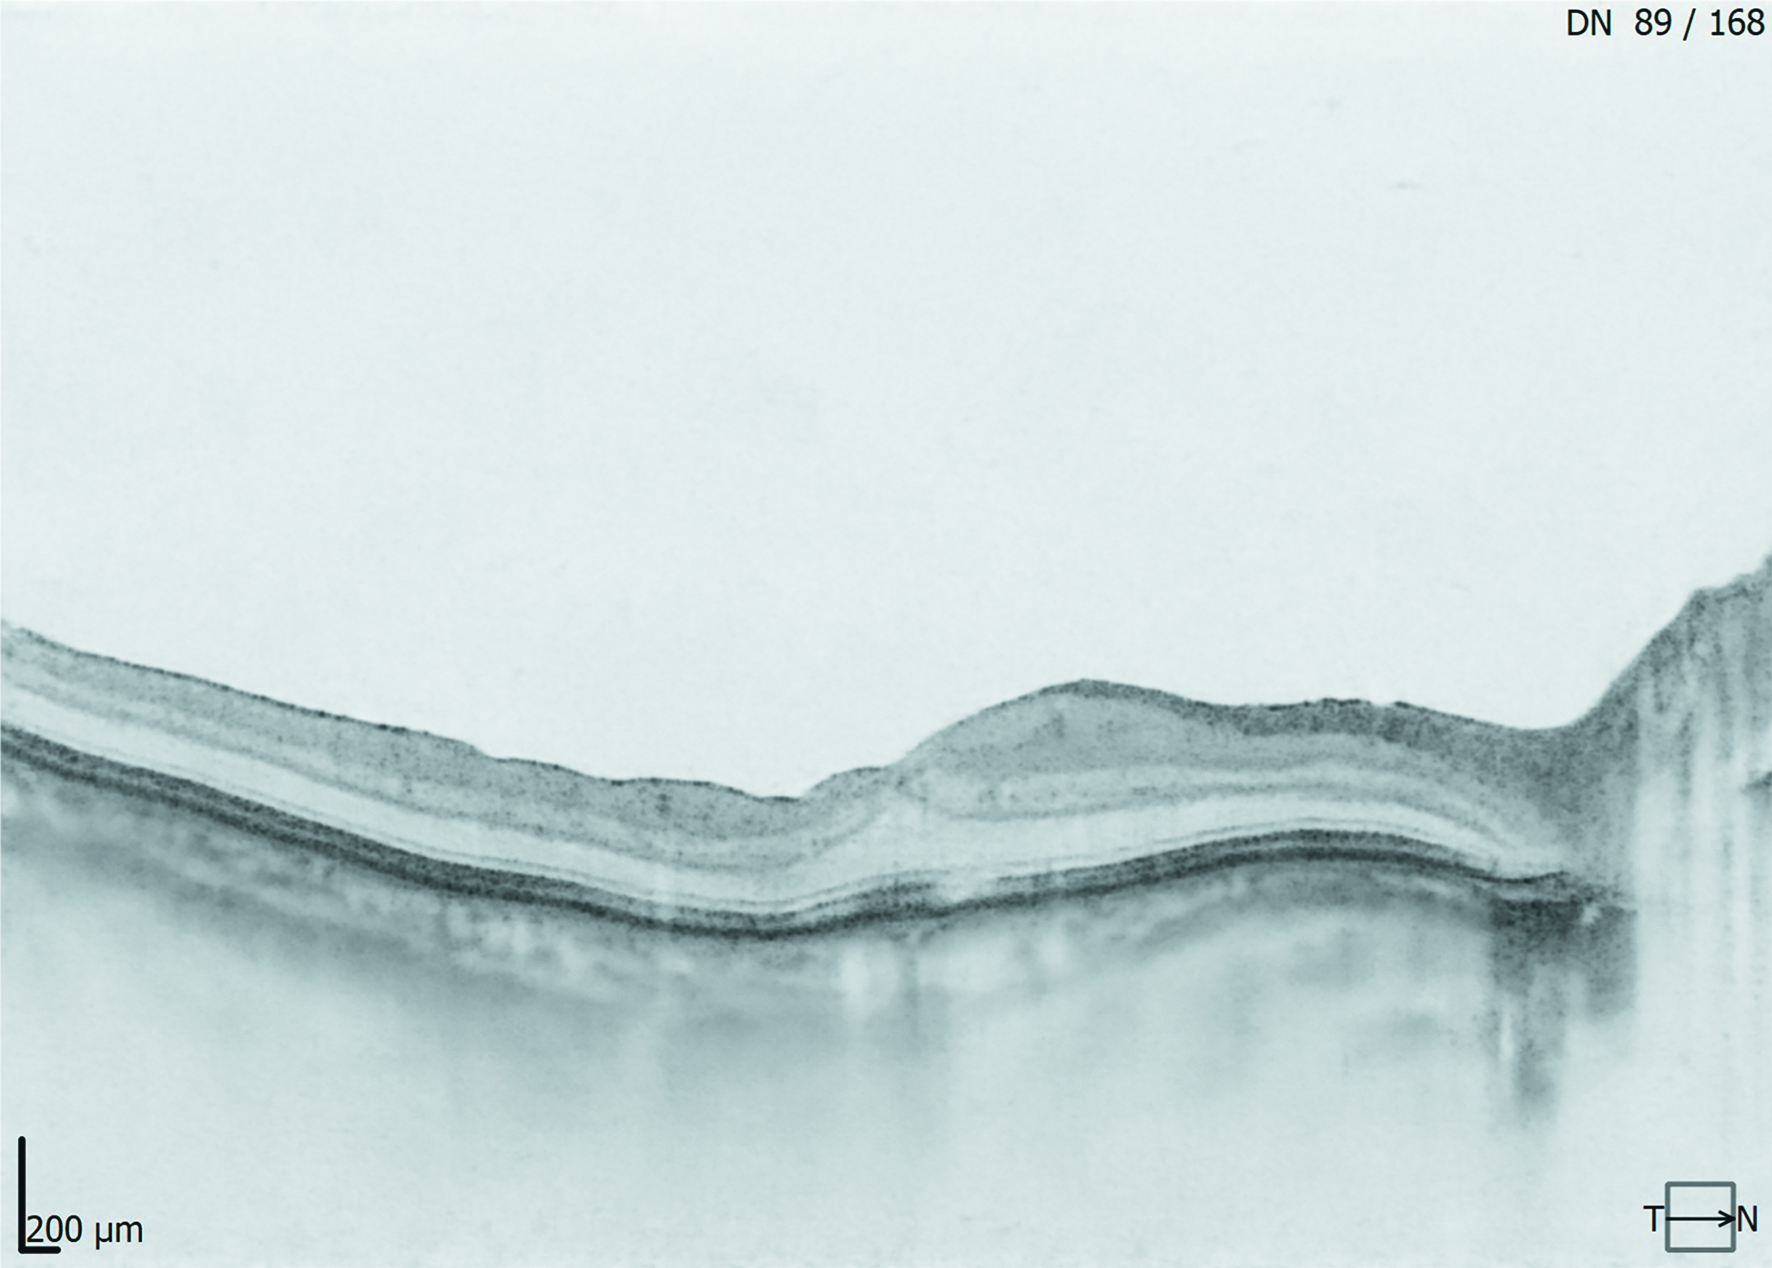

Через 3 месяца после операции толщина сетчатки в макулярной области равнялась 333,5 (311,5; 503) (р=0,068704). Отсутствие статистической значимости в уменьшении МО спустя три месяца после супрахориоидального введения ТА объясняется тем, что у 3 из 8 пациентов (37,5%) спустя 3 месяца произошел рецидив МО, в связи с чем пациентам было предложено повторить введение препарата. Тем не менее, МКОЗ через 3 месяца послеоперационного наблюдения достоверно повысилась и составила 0,6 (0,25; 0,9) (р=0,043115). ВГД равнялось 18,0 (15,5; 20,5) и статистически значимо не отличалось от исходных значений (р=0,105646). У 5 из 8 пациентов (62,5%) в течение 3 месяцев был достигнут стабильный положительный результат в виде купирования МО (рисунки 4, 5).

Рисунок 4. Пациент К., диагноз «Макулярный отек. Оперированная отслойка сетчатки. Авитрия». МКОЗ до операции 0,1 н/к. Толщина сетчатки в макулярной области по данным ОКТ макулы до операции 728 мкм

Figure 4. Patient K., diagnosis «Macular edema. Operated retinal detachment. Avitria». BCVA before operation was 0,1. Retinal thickness in the macular area according to OCT results before operation was 728 µm

Рисунок 5. Пациент К., 6 месяцев после операции. МКОЗ= 0,9 н/к. Толщина сетчатки в макулярной области по данным ОКТ макулы 311 мкм

Figure 5. Patient K., 6 months after surgery. BCVA=0.9. Retinal thickness in the macular area according to OCT results is 311 µm